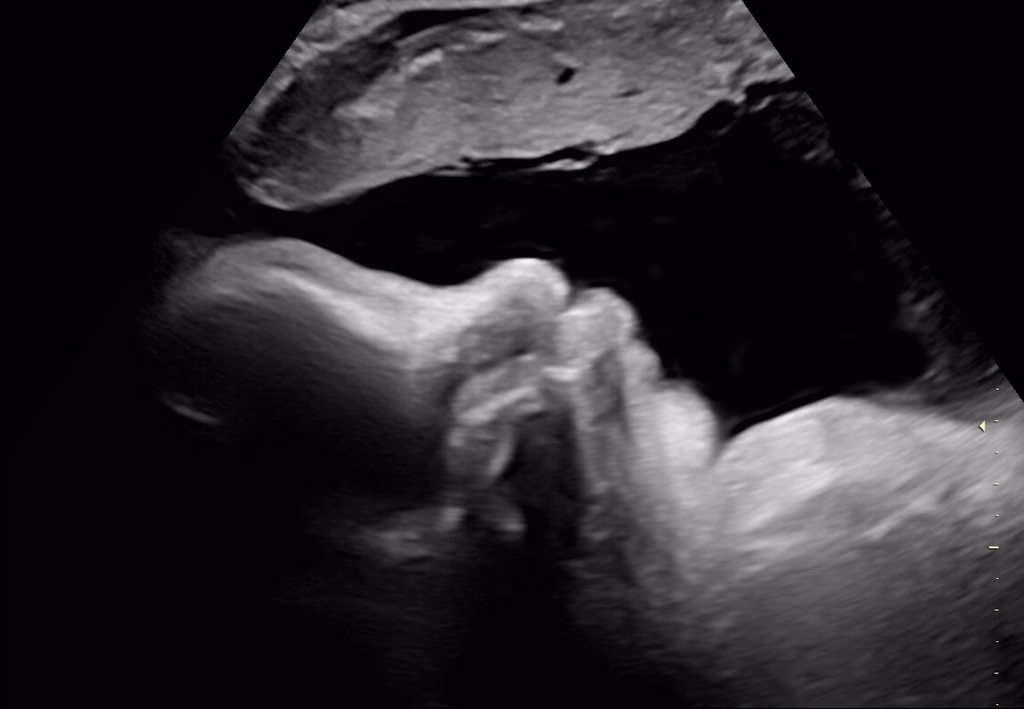

Vid ultraljud i första trimestern dateras graviditeten och du får ett beräknat förlossningsdatum. Fostret är nu cirka 6-7 cm mellan huvud och rumpa (CRL, Coronary Rump Lenght).

Vi kontrollerar antal foster, hjärtaktivitet och fostervattenmängd. Fostrets anatomi granskas noggrant för att upptäcka eventuella avvikelser, och moderkakans läge bedöms. Undersökningen görs via magen.

Rutinultraljudet görs via magen i graviditetsvecka 19 för att gå igenom anatomin på fostret enligt en checklista, titta var moderkakan sitter, kontrollerar hjärtaktivitet, fosterrörelser samt mängden fostervatten. Har du inte gjort något tidigare ultraljud sätts ett beräknat förlossningsdatum i samband med rutinultraljudet och vi tittar på hur många foster det är i magen.

Vid det här ultraljudet är fostret cirka 20 cm och vi kan också se vad det är för kön, om du vill veta det.